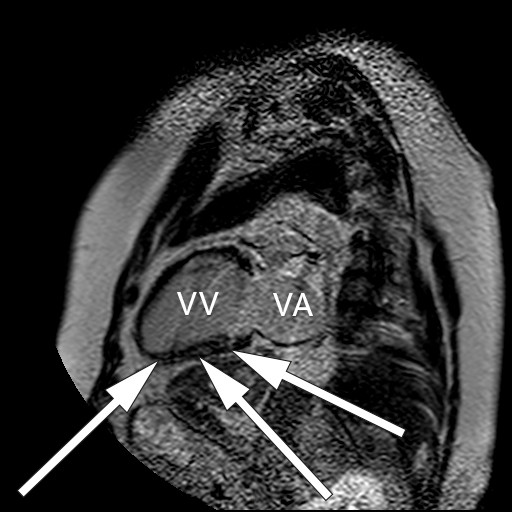

Som ved alle andre undersøkelser er sensitivitet og spesifisitet avhengig av sykdommens prevalens, undersøkelsesmetode og legen som vurderer resultatet av undersøkelsen. Ved MR cor kan man oppdage både inflammatoriske og fibrotiske forandringer som er assosiert med kardial sarkoidose (fig 1–3) (7).

Den aktive, inflammatoriske sykdomsfasen kjennetegnes av økt gadoliniumkontrastopptak ved tidlig undersøkelse og veggfortykkelse som oppstår sekundært til granulomatøs infiltrasjon og ødem (6, 7). Dersom pasientene har utviklet fibrotiske forandringer, vil MR-undersøkelsen vise kontrastopptak ved sen undersøkelse, kalt sen kontrastutvasking (4). Fibrotiske forandringer ved MR-undersøkelse kan være en prognostisk markør som er assosiert med ventrikulære arytmier og mortalitet (4). Fibrosen forekommer som regel ikke i klassiske arterielle forsyningsområder, i motsetning til ved aterosklerotisk hjertesykdom (5). I tillegg vil kontrastoppladningen ved et hjerteinfarkt alltid involvere subendokard (med varierende grad av transmuralitet), mens ved kardial sarkoidose kan kontrastoppladningen forekomme i alle deler av myokard (6).